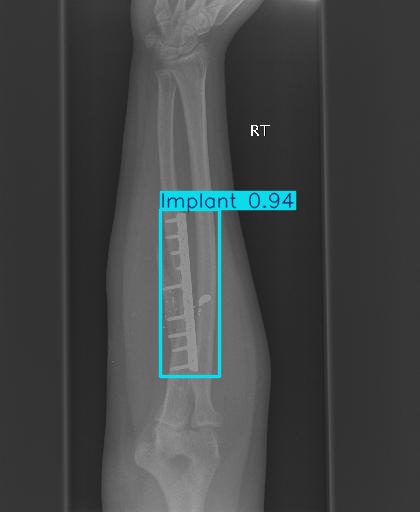

20251204_01 predict

class 이름을 반대로 해뒀다...

| imgsz | 800 | 뭔가 train이랑 같아야할 것 같아서 같이 바꿨다 |

| conf | 0.3 | 원래 0.9였는데 어제 결과가 너무 안 나와서 0.5로 바꿨다가 다시 0.3으로 바꿨다 |

20251204_02 predict2

진짜 라벨링 문제였나보다